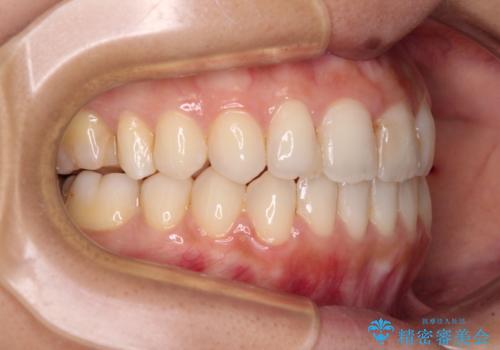

オープンバイトによる見た目を治したい インビザラインでの矯正治療

- オープンバイトのため、話しているときの見た目が気になるとのことで来院された患者様です。

下顎骨は左側にシフトしており、咬み合ったときには奥歯と前歯の一部しか接触していない状態でした。

骨格的な左右差は歯列矯正は改善できないため、上下歯列が全体的に接触することをゴールとしてインビザラインにて矯正治療を行うこととしました。

前歯のデコボコの解消と並行して上下の奥歯を圧下させるようにすることで、前歯を接触させるように計画しました。

上下の隙間に舌が入り込むことがオープンバイトの原因であったため、舌の筋肉のトレーニングも並行して行い、後戻りの抑制を図りました。